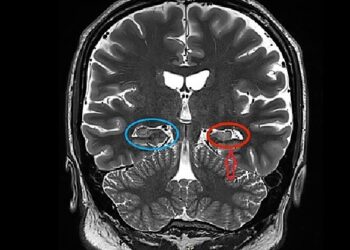

The adrenal glands also release which neurotransmitter?

Adrenaline